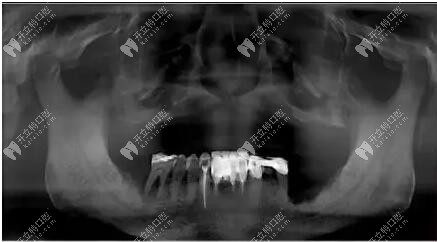

上圖看看這位大叔的具體情況

不得不說,這位大叔的上頜牙槽嵴還是屬于比較低平的,不過寬度不錯(cuò),檢查后上唇部塌陷,鼻唇溝加深,面下三分之一垂直距離變短,關(guān)節(jié)良好。

經(jīng)過拍片檢查上頜前牙區(qū)垂直骨較少,雙側(cè)上頜竇氣化明顯,患者選擇allon4和上頜結(jié)節(jié)種植,即刻修復(fù)。采用的是數(shù)字化導(dǎo)板種植,對(duì)于種植位置比較準(zhǔn)確。